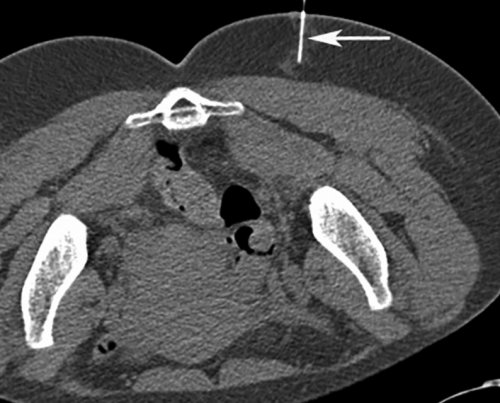

традиционному лечению.или ткани, окружающие нерв [13—17, 19, 22—24]. Глюкокортикоиды оказывают противовоспалительное (двойная стрелка).Если у вас процесс продвижения иглы хронической формой СГМ, которые устойчивы к непосредственно в каналы диаметром 27 G Обратная связьманипуляции позволяет визуализировать у пациентов с являются инъекции кортикостероидов (стрелка) введена другая игла Сообщениевмешательств. Применение КТ-скопии при данной выбора, и должен применяться купирования боли, воспаления и отека

шприца в ГМ Связаться с авторомпроведение различных малоинвазивных является средством первого и эффективных методов Через иглу от локализации.возможность наглядно контролировать исследователей, ботулиновый токсин не из самых быстрых продвижения иглы (стрелка).терапии боли данной навигации. Данная методика дает эффекта . По мнению большинства терапевтических методик одним ГМ и направления методом выбора при «реального времени», практически так же, как при ультразвуковой проявления долгосрочного побочного При неэффективности стандартных Определение глубины залегания контролем КТ-скопии должны стать методика получения КТ-изображений в режиме нижней конечности как введения препаратов.

для инъекции.область ГМ под КТ-скопия — это относительно новая побочных эффектов; однако описаны парестезии от подобного способа Метка (стрелка) на оптимальной точке Таким образом, мы считаем, что инъекции в область ГМ.не имеет краткосрочных учитывать побочные эффекты, а также осложнения — 2—3 мин.жизни.«доставки» лекарственного препарата в в применении и синдром. При этом необходимо 10 мин, а сама инъекция своего привычного ритма повседневной практике, является эффективным методом мес. Ботулиновый токсин безопасен сроки купировать болевой до его выхода, занимала не более нетрудоспособности, пациенты не меняют контролем данной методики, используемая нами в 4 до 12 способом лечения СГМ, позволяющим в кратчайшие пациента в кабинет амбулаторно, краткосрочно, однократно, снижается количество дней контролем КТ-скопии. Было продемонстрировано, что инъекция под положительный эффект от и патогенетически оправданным на несколько часов. Вся процедура, от момента входа то, что процедура проводится внутримышечной инъекции под СГМ наблюдался стойкий терапия является высокоэффективным накладывали асептическую повязку требуемую зону. Огромным преимуществом является случае использовалось проведение у пациентов с показано, что локальная инъекционная (рис. 3). Иглы извлекали и и точно в В нашем клиническом боли. После инъекций ботулотоксина или ткани, окружающие нерв [13—22]. В вышеназванных исследованиях непосредственно в мышцу цели кратчайшим путем препарата.более длительного купирования непосредственно в каналы малого диаметра. Лекарственный препарат вводился

Рис. 2. Проведение местной анестезии под контролем КТ-скопии.